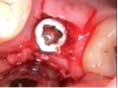

Under local anesthesia, a full thickness flap was elevated from the upper right to upper left posterior segments. Using a piezoelectric handpiece, a buccal window hinge osteotomy was elevated in the maxillary right posterior region. A mixture of DFDBA, anorganic bovine bone, and PRF was placed. A collagen membrane was used to cover the buccal window. Simultaneously, two puros J-block allografts were secured in the 5 to 7 and 10 to 12 region with stainless steel screws (1.6 x 8 mm screws). A mixture of DFDBA, anorganic bovine bone and PRF was placed over each area and covered with PRF sheet and a collagen membrane. Primary closure was obtained with CV-5 Goretex sutures. Healing was uneventful. After six months of healing, six straight implants were placed in sites 3, 4, 5, 6, 11, and 12. Healing abutments were placed at stage I. Healing was uneventful. After four months of healing, six custom abutments were fabricated by his dentist and cover screws were placed on implants 8 and 9 and converted into pontics.

Case 2: Sinus lift, bone graft, PRP, and after healing implant placement